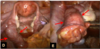

Descreva os achados desta imagem e cite o provável diagnóstico

Complicação da DIP

- Abscesso tubovariano